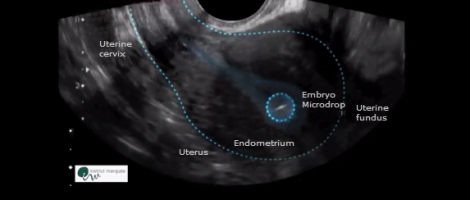

In the following ultrasounds the microdrop moves through the endometrial cavity with different undulating, vibratory, slow, fast movements and with resting stages.

In all cases, it is confirmed how the embryos have changed its position with regard to the distance from the uterine fundus after one hour, where it was initially deposited, regardless whether it was 1, 2 or 3 cm away or not.

The discovery shows that it is not necessary the patient rests absolutely and allows to change the medical guideline which is given to the patients after embryo transfer. And, consequently, to reduce the stress it generates, since after transfer women feel so much pressure in case embryos are expelled when they move.